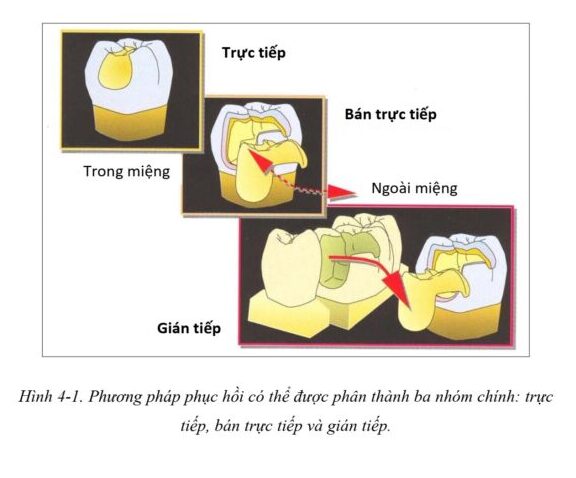

Các kỹ thuật phục hồi thẩm mỹ cho răng sau có thể được phân loại thành ba nhóm (H4-1): các kỹ thuật “trực tiếp” chỉ bao gồm các thủ thuật trong miệng và thực hiện trong một lần hẹn duy nhất, kỹ thuật “bán trực tiếp” bao gồm các bước trong miệng hoặc ngoài miệng để tạo ra các phục hồi tại ghế, sau đó gắn trong cùng lần hẹn, và kỹ thuật “gián tiếp”, yêu cầu một vài lần hẹn và sự hợp tác của labo để chế tác phục hồi.

Những thuật ngữ này (trực tiếp, bán trực tiếp và gián tiếp) giúp đơn giản hóa và làm rõ việc phân loại nhiều quy trình phục hồi hiện nay cũng như các chỉ định tương ứng của chúng.

Các bác sĩ lâm sàng đều đồng ý rằng, kĩ thuật phục hồi trực tiếp chỉ nên thực hiện cho những lỗ sâu có kích thước từ nhỏ đến trung bình (H4-4 a-d)

Những xoang I, xoang II có kích thước lớn cũng như những phục hồi bán phần thì thường ưu tiên chỉ định phục hồi dán, lý tưởng nhất là có thể khôi phục một răng đơn lẻ hoặc một số răng giới hạn (hai đến ba răng phân bố trong các phần hàm khác nhau) bằng cách sử dụng kỹ thuật bán trực tiếp.

Nếu phải điều trị nhiều răng trên dưới cùng một lúc thì thường khó tạo được hình thể mặt nhai đúng giải phẫu và khớp cắn chức năng do các quy trình cơ bản của kỹ thuật bán trực tiếp như điêu khắc mặt nhai mà không có răng đối kháng phù hợp. Do đó, các kỹ thuật gián tiếp nên được chỉ định cho phục hồi toàn bộ cung răng hoặc từng phần hàm (H4-4 i-l).

Các phục hồi dán được thực hiện tại labo sẽ giúp kiểm soát khớp cắn và đạt thẩm mỹ tốt hơn. Đối với những phục hồi mở rộng (onlay hoặc overlay) thì thực hiện bằng kỹ thuật gián tiếp cũng được khuyến cáo.